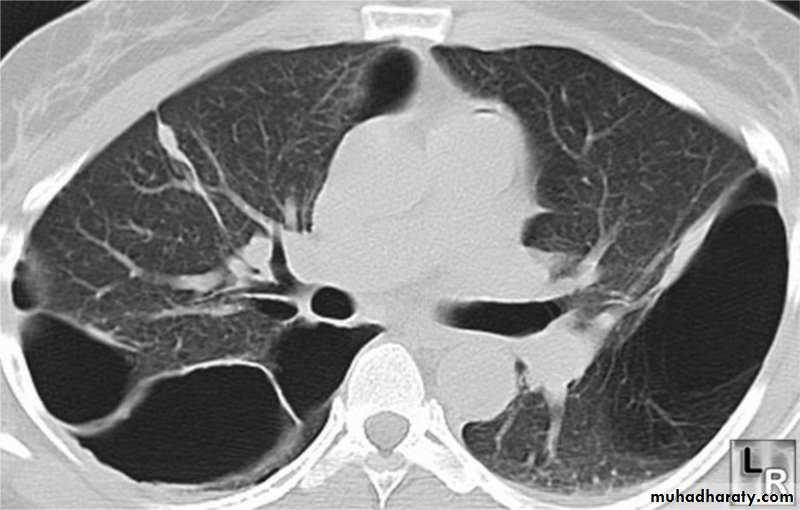

Investigations Imaging

High resolution CT scan (HRCT) is the definitive test to exclude the diagnosis of emphysema. However, this is only required when planning for surgeryInvestigations